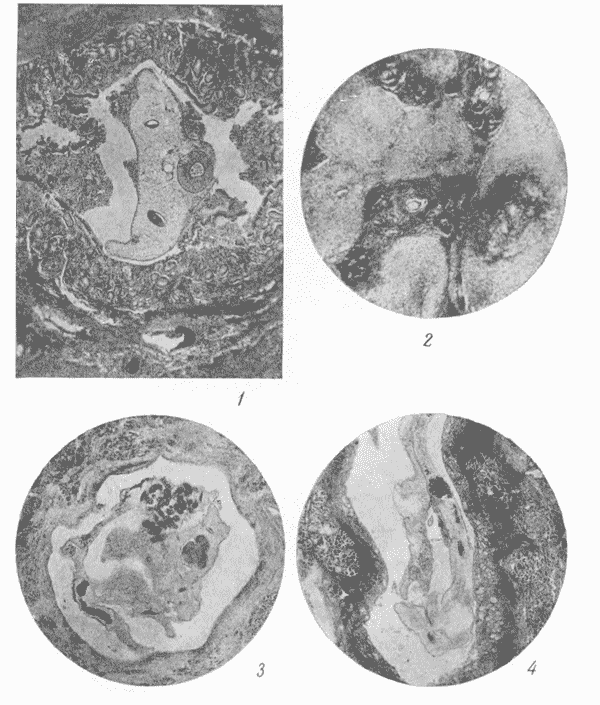

Патологическая гистология при описторхозе человека (по Н. Н. Плотникову).

1 — локализация Opiathorchis felineus в желчном протоке печени человека; 2 — разрастание соединительной ткани печени при описторхозе человека; 3 — проток поджелудочной железы человека, заполненный Opisthorchis felineus; 4 — описторхоз поджелудочной железы человека. В просвете протока железы локализуется Opisthorchis felineus с ясно выраженной ротовой присоской и фаринксом